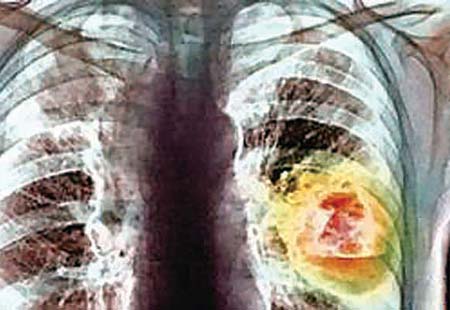

Thuốc mới chống ung thư phổi

Theo tạp chí Lancet oncology, TG4010- một loại thuốc dạng chích chống ung thư phổi qua thử nghiệm ở 148 bệnh nhân đã cho kết quả khả quan. Sau 6 tháng thử nghiệm loại thuốc do Đại học Strassbourg (Pháp) điều chế, người ta thấy 43% bệnh nhân có thuyên giảm so với 35% chỉ dùng hóa trị.

Thuốc này dùng chung với biện pháp hóa trị đã giúp kích thích hệ thống miễn dịch tấn công tế bào ung thư tốt hơn. Tuy nhiên, các nhà khoa học cho biết cần có thêm nghiên cứu trước khi sử dụng chính thức.